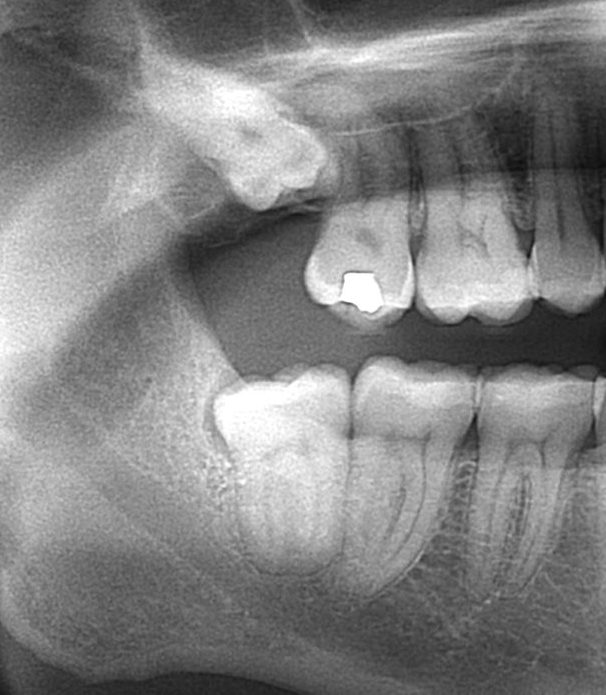

Infected wisdom tooth

Our patient had an infected lower wisdom tooth that was causing pain, discomfort, and inability to chew food.  Patient elected just to extract the lower wisdom tooth causing her issues.